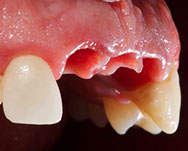

Fig. 12-13-14: Every demanding aesthetic treatment involving implants should have a provisional phase before the definitive prosthesis is delivered. It is mandatory to design natural emergence profiles before finishing the treatment.

7) Managing provisionals in implants in the aesthetic zone. Current concepts.

During the provisional phase of the treatment, a correct and natural emergence profile should be created following the adjacent tooth.